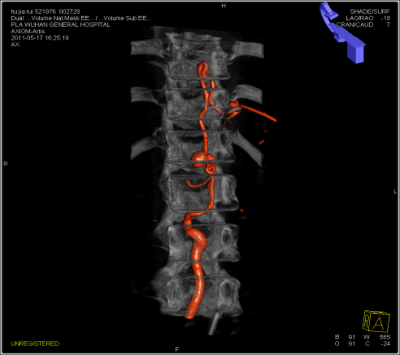

DynaCT双容积成像可以对不同容积影像如支架、弹簧圈、血管等同时显示,指导医生对支架释放、治疗预后进行评估。

血管,介入材料,骨骼的双容积成像,分辨三维空间中的位置关系,以及动静脉双血管的融合。